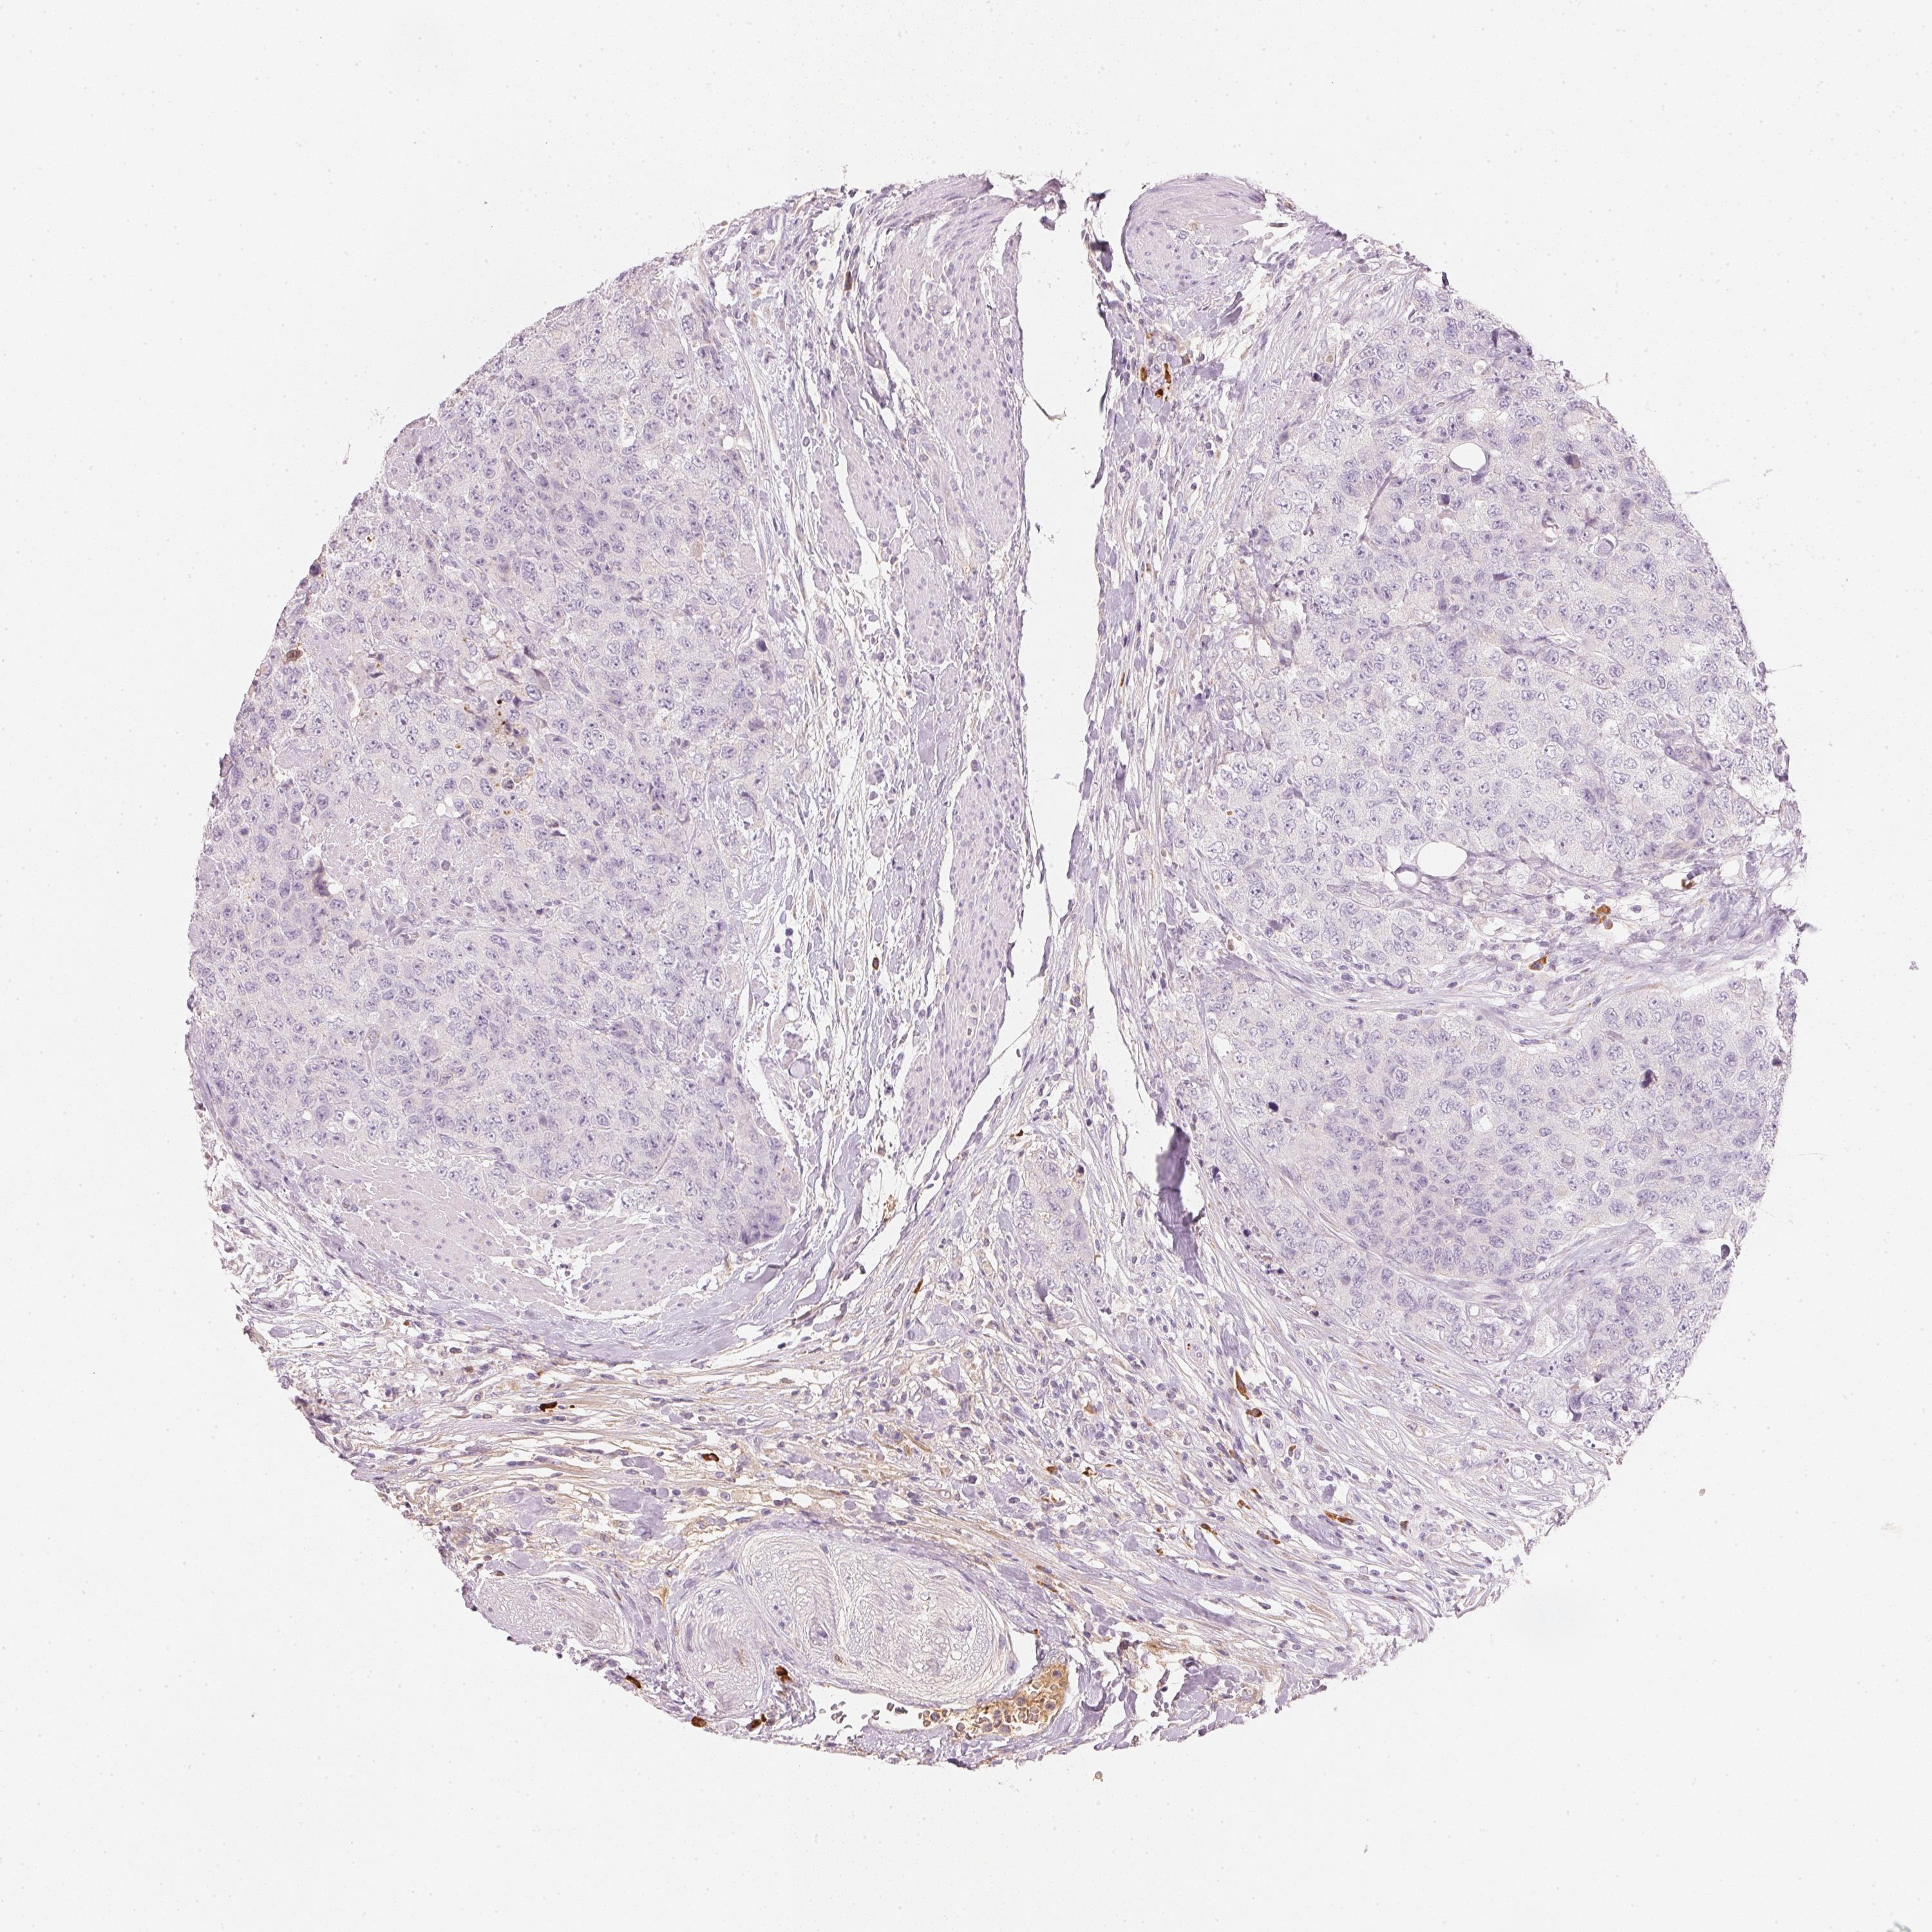

UROTHELIAL CANCER - Protein expressioni

A mouse-over function shows sample information and annotation data. Click on an image to view it in a full screen mode. Samples can be filtered based on level of antibody staining by selecting one or several of the following categories: high, medium, low and not detected. The assay and annotation is described here.

Antibody stainingi

Antibody staining in the annotated cell types in the current human tissue is reported as not detected, low, medium, or high, based on conventional immunohistochemistry profiling in selected tissues. This score is based on the combination of the staining intensity and fraction of stained cells.

Each image is clickable and will lead to virtual microscopy that enables deeper exploration of all samples and also displays staining intensity scores, fraction scores and subcellular localization as well as patient and tissue information for each sample.

Antibody HPA034705

Antibody HPA034706

Staining

High

Medium

Low

Not detected

Intensity

Strong

Moderate

Weak

Negative

Quantity

>75%

75%-25%

<25%

None

Location

Nuclear

Cytoplasmic/membranous

Cytoplasmic/membranous,nuclear

Urothelial carcinoma, High grade

Urothelial carcinoma, Low grade

Urothelial carcinoma, NOS